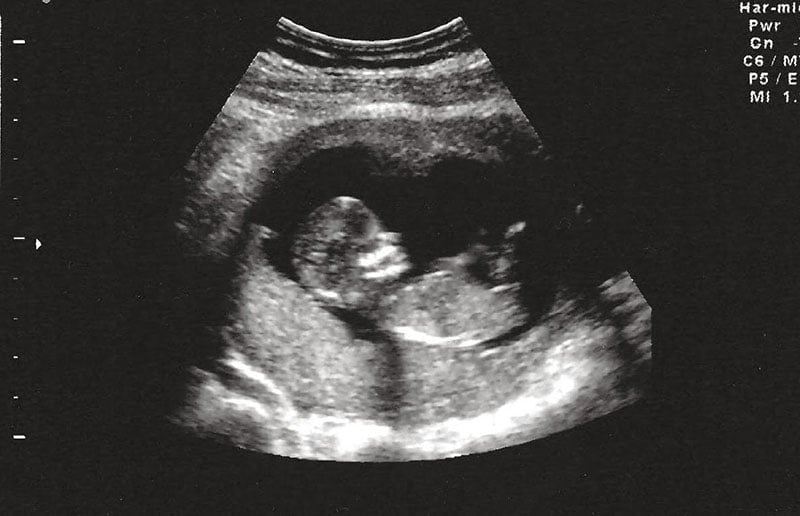

Đến lần mang thai thứ 5, em làm xét nghiệm NIPT, kết quả bình thường, em thở phào nhẹ nhõm. Em tin, có lẽ ông trời đã thương. Nhưng đến tuần thứ 20, bác sĩ nói chân tay con bị khèo… rồi mọi hy vọng lại sụp đổ thêm lần nữa.

"Lúc cầm tờ kết quả xét nghiệm chẩn đoán, em chỉ biết khóc. Không còn nước mắt nào đủ để rơi nữa." Lần này, em làm NIPT kèm xét nghiệm sàng lọc gen, em mới biết cả hai vợ chồng đều mang cùng một gen bệnh lặn – và có 25% khả năng con sinh ra bị bệnh di truyền. Bác sĩ bảo, đó chính là nguyên nhân khiến con không thể ở lại.

Bao gồm: Double test, Triple test, NIPT, siêu âm hình thái, v.v.

Nếu có nghi ngờ bất thường, bác sĩ sẽ chỉ định thêm xét nghiệm di truyền chuyên sâu hoặc xét nghiệm gen của bố mẹ.